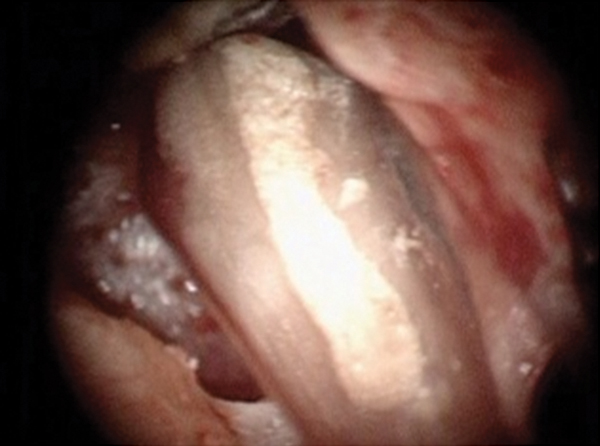

Fig 16. Post apicoectomy. Courtesy of Dr. Sam Kratchman.

Figure 16

Case 3: Apicoectomy and Retrofill

A patient presented with clinical symptoms and radiographic signs of post-endodontic disease (Figure 15). It was determined that the ledge on the mesial canals precluded retreatment and that an apicoectomy was to be performed. After locating the apicoectomy, it was possible to visualize both canals and an obvious isthmus between the two main canals (Figure 16). Retro-preparations were performed in the main canals, and the isthmus between them was grooved and the cavities filled with BC RRM-Putty (Figure 17). At the 20-month follow-up, the patient was asymptomatic and the radiograph showed complete healing (Figure 18).